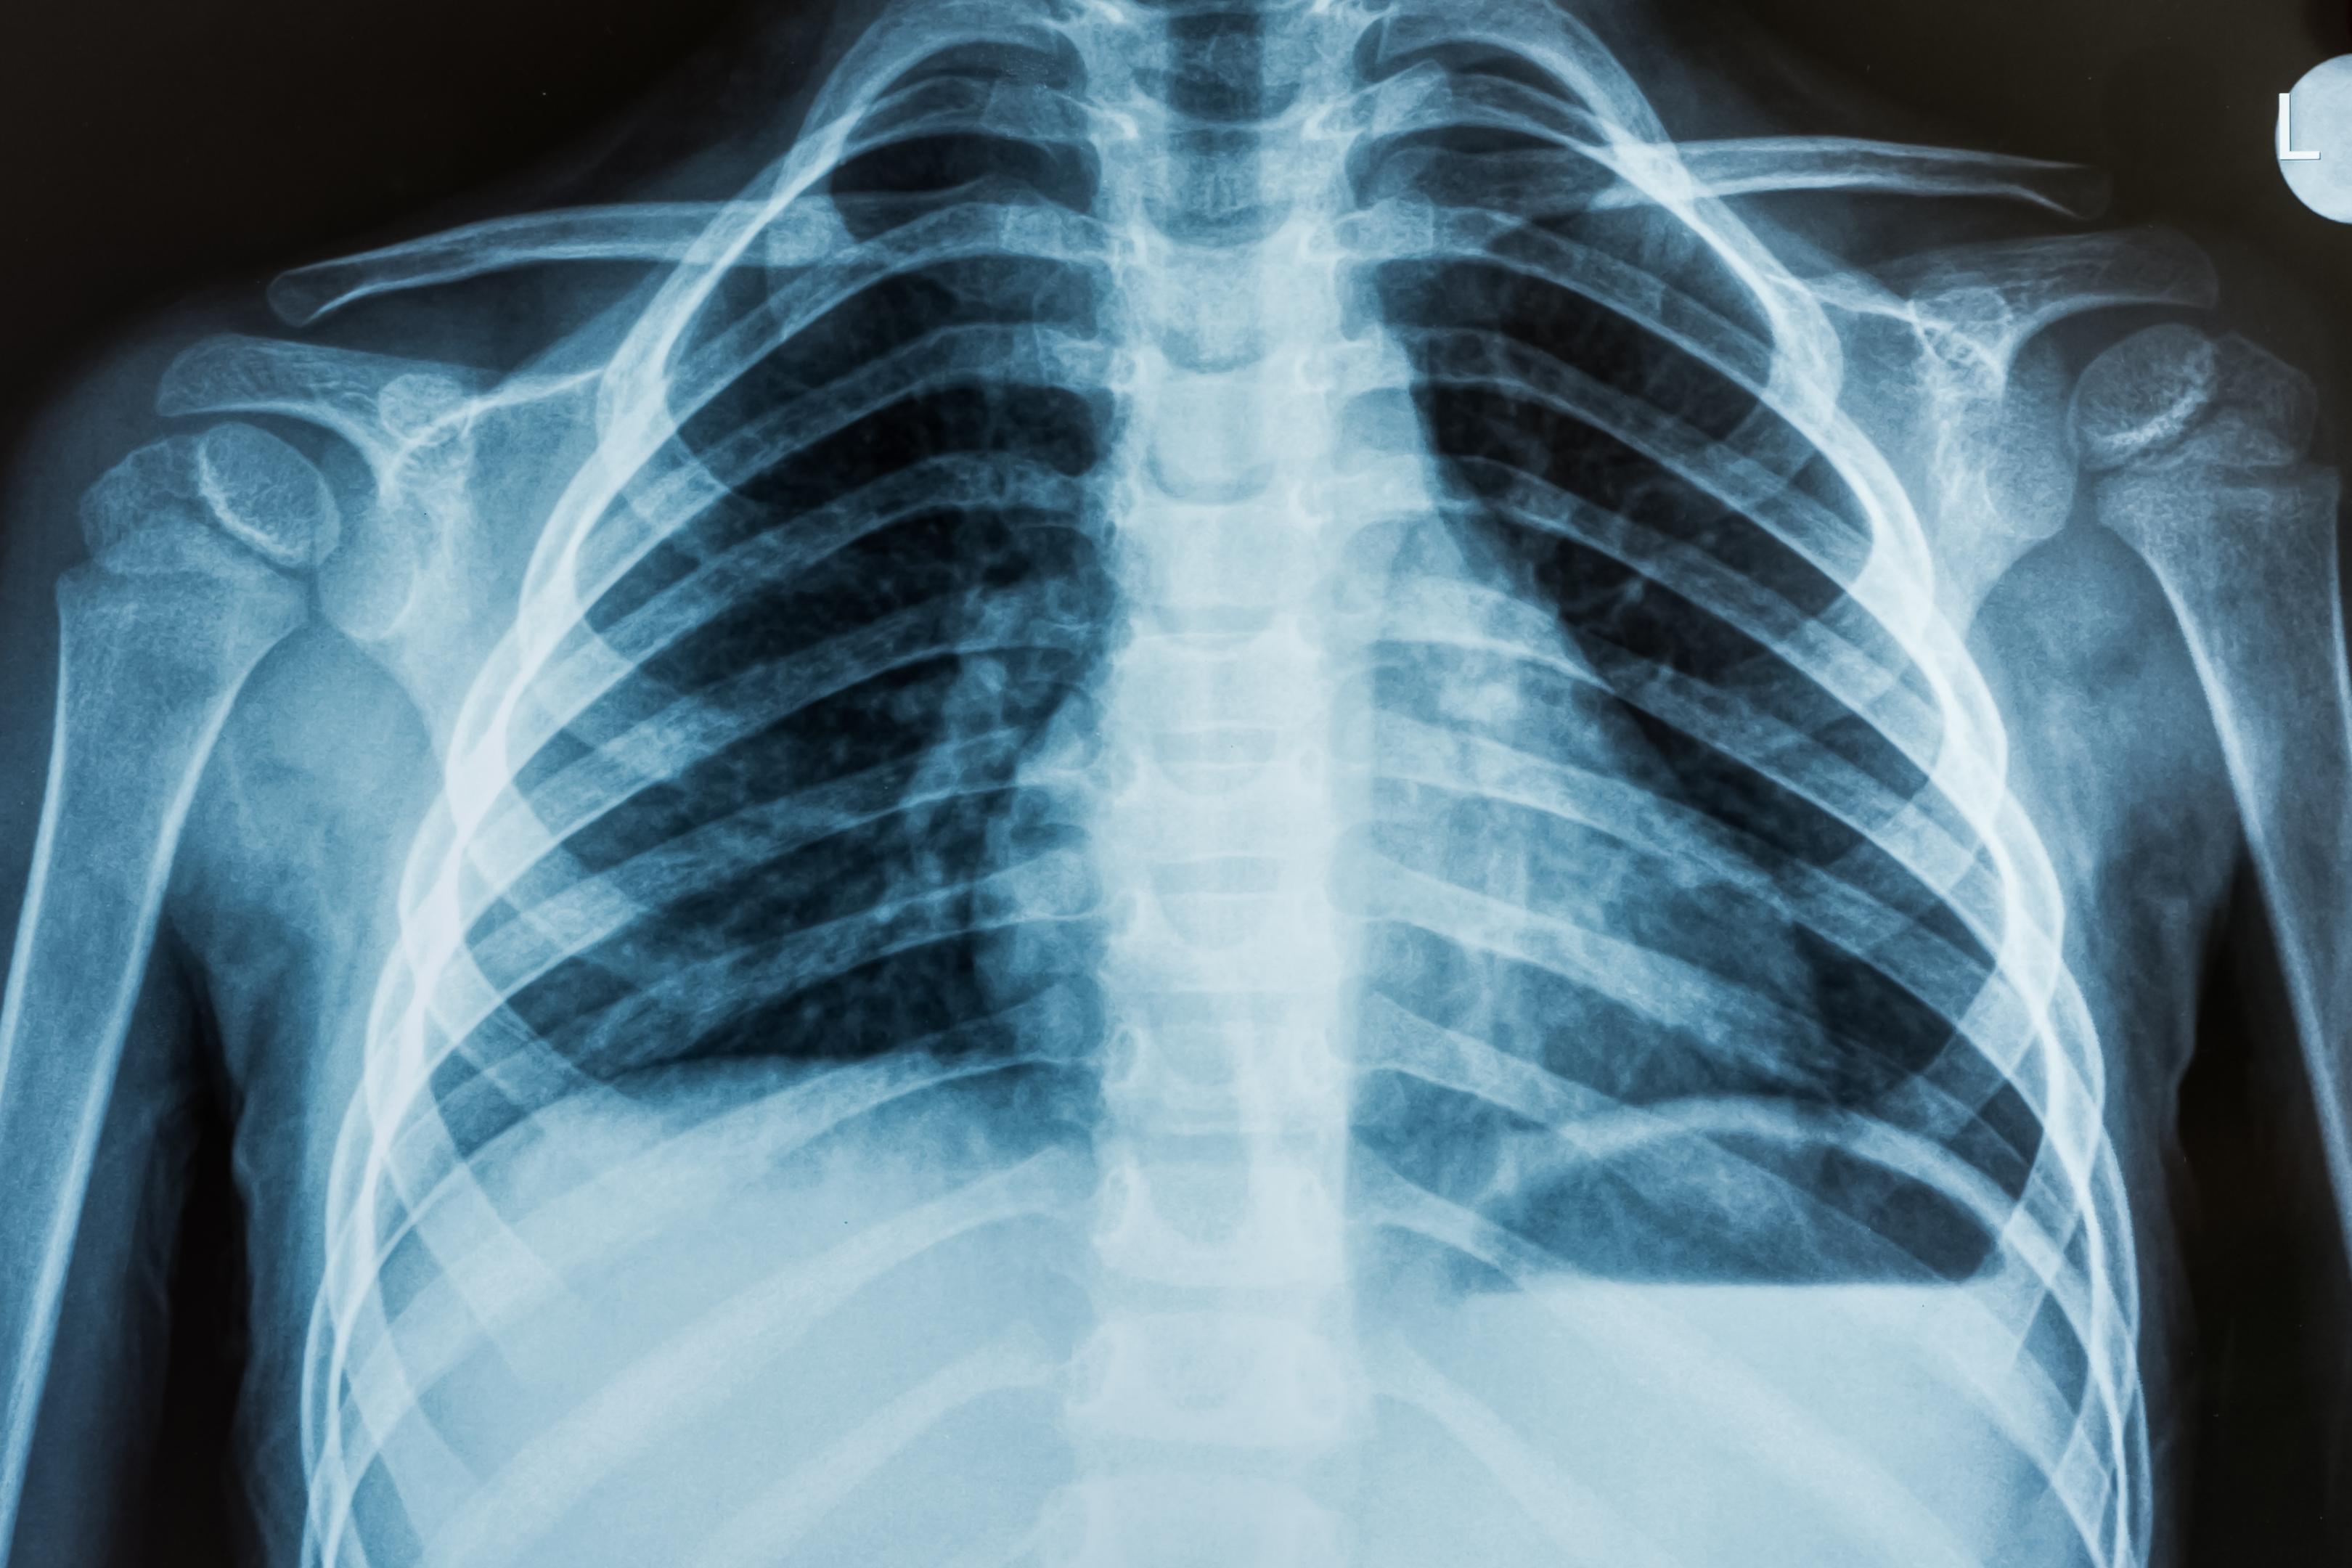

X-ray imaging works by passing a beam of X-rays through the body, with the energy of the X-rays absorbed or scattered by the tissues they pass through. The resulting image shows areas of different tissue density, allowing doctors to identify abnormalities such as fractures, tumors, and other conditions.

X-ray imaging is most commonly used to diagnose skeletal and chest conditions. For skeletal conditions, X-rays can help identify fractures, dislocations, and bone deformities. In chest X-rays, doctors can identify lung conditions such as pneumonia, lung cancer, and other respiratory issues.